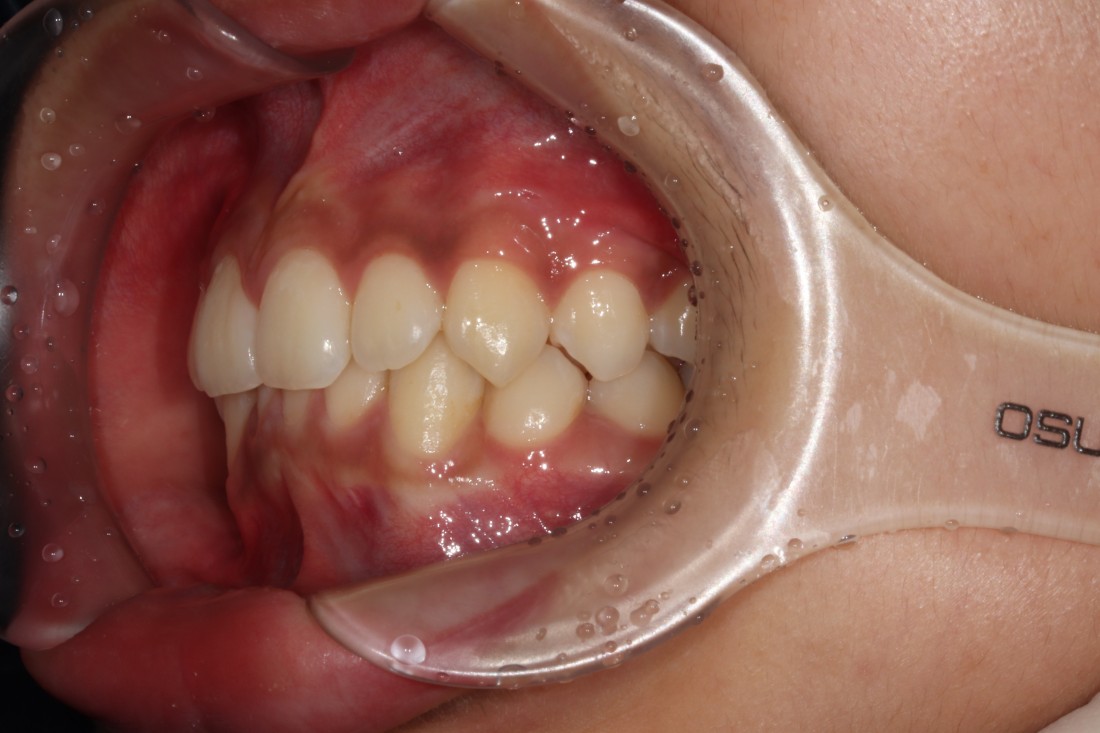

윗니에 아랫니가 거의 덮여있는

과개교합의 경우에는

턱관절 장애를 유발합니다.

성인이 된 이후에도

과개교합을 방치하게 되면

앞니가 많이 마모되게 되며,

사각턱이 생길 수 있으며

무엇보다 교합이 맞지 않기 때문에

시간이 지날수록 턱관절장애를 유발하게 되어

빠르게 개선해주는 것이 좋습니다.